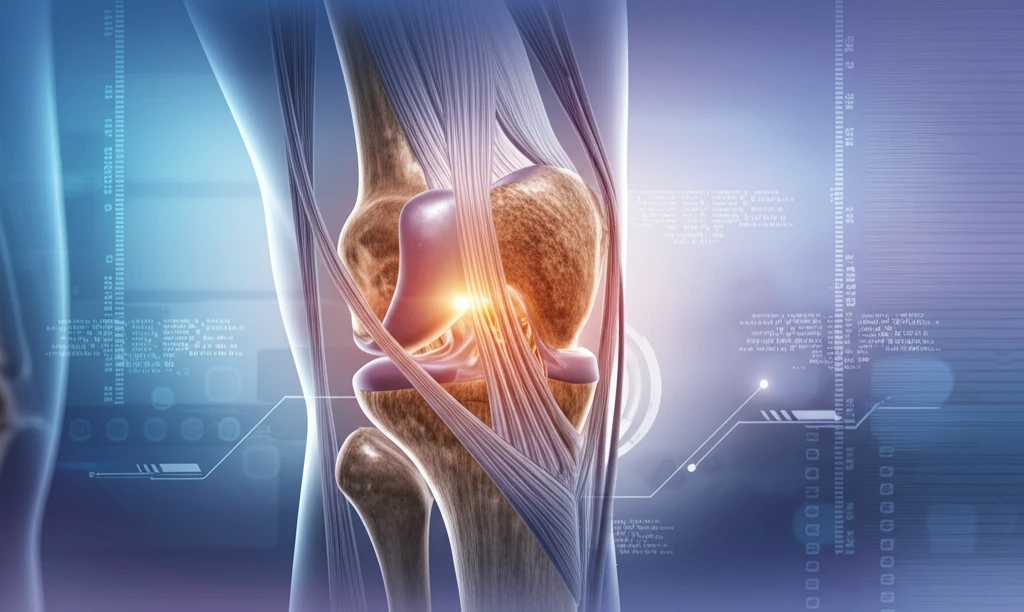

The knee is a complex joint. It relies on both bone and soft tissue to function correctly. When things go wrong with the patellofemoral joint (the area where your kneecap sits), it can lead to instability or persistent pain.

If you're dealing with patellofemoral issues, careful assessment through clinical exams and imaging is key. Cross-sectional imaging like MRI plays a vital role in planning any potential surgery.

Surgical treatments for patellofemoral problems can address soft tissue, bone issues, or both. This article explains what happens after surgery, focusing on imaging results of the knee's extensor mechanism. We'll cover common procedures, why they're done, and possible complications, empowering you to understand your recovery.